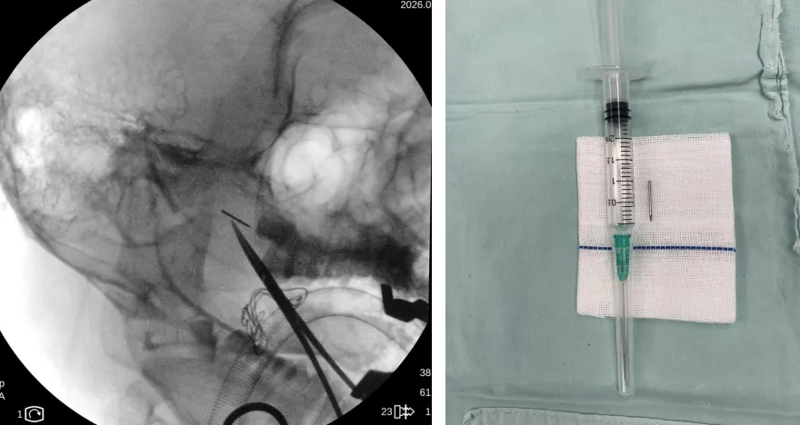

接诊医生唐亮主任医师为患者进行详细检查,发现患者面部多发红色丘疹、皮肤硬结及白色脓疱状丘疹,双颊、颏部有明显色素沉着,右侧面颊局部红肿、触痛明显,但体表未触及明确异物。结合患者病史及症状,医生判断,断针残留已引发明显的面部软组织炎症反应,若不及时取出,断针可能进一步移位,损伤面部神经、血管或腮腺等重要组织,后果不堪设想。同时,患者及家属明确提出美容取针需求,希望尽可能减少面部疤痕。为精准定位断针位置,耳鼻咽喉头颈外科团队为患者进行CT三维重建检查,结果显示,一枚长约1.6cm的断针深埋于患者面部软组织内。针对患者情况,科室迅速组织术前讨论,联合手术麻醉中心等相关科室团队制定个性化治疗方案,最终决定在气管插管全麻下,借助C臂X光机引导,经口实施手术取异物,并同步开展右颌面部修复处理,既确保断针完整取出,又最大限度兼顾面部美观。

手术过程充满挑战,由于患者面部炎症明显、软组织肿胀,断针暴露差,给寻找和取出工作带来难度。术中,手术团队在C臂X光机的精准引导下,通过经口右侧颊部近后磨牙处约2cm的切口逐步探查,凭借精湛的显微操作技术,用显微组织钳多次调整角度,缓慢接近异物,最终在眼科异物磁吸器的协助下,于腮腺内前方成功找到断针,并将这枚长约1.6cm的断针完整取出。术后检查确认,患者脸部无异物残留、无组织锈迹及活动性出血,也未造成腮腺组织损伤。